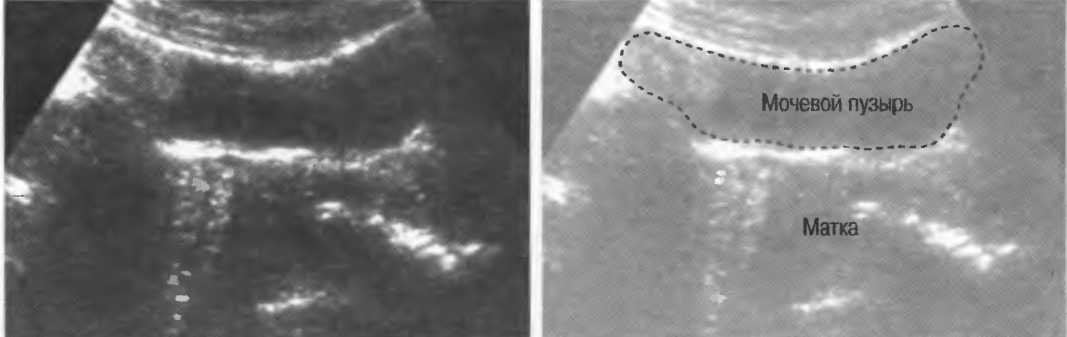

Рис.11. Изображение матки при использовании датчиков разной частоты. Качество лучше оценивается при исследовании структур эндометрия. В наполненном мочевом пузыре определяются реверберации.